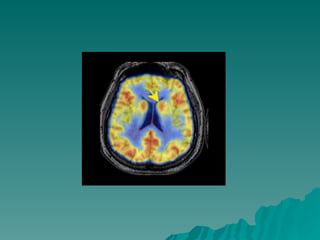

Caudate, Putamen, and Globus Pallidus Volume in Schizophrenia: A Quantitative MRI Study   Hiroto Hokama, M.D.1, Martha E. Shenton, Ph.D.1, Paul G. Nestor, Ph.D.1, Ron Kikinis, M.D.2, James J. Levitt, M.D.1, David Metcalf, M.A.2, Cynthia G. Wible, Ph.D.1, Brian F. O'Donnell, Ph.D.1, Ferenc A. Jolesz, M.D.2 and Robert W. McCarley, M.D.3 ABSTRACT Basal ganglia structures have been reported to be abnormal in schizophrenia, However, while component structures of the basal ganglia are functionally  differentiated, there have been no evaluations of their separate MRI volumes using small voxel (1.5 mm3) SPGR techniques and multi-plane assessments. We examined MRI scans from 15 male, right-handed neuroleptic-medicated schizophrenics and 15 age, handedness, and gender-matched normal controls. Compared to controls, schizophrenics showed enlarged volumes: 14.2% for total basal ganglia, 27.4% for globus pallidus, 15.9% for putamen and 9.5% for caudate. Increased volumes, especially caudate, were ssociated with poorer neuropsychological test performance on finger tapping and Hebb's Recurring Digits. These findings indicate abnormalities throughout all basal ganglia structures in at least a subgroup of schizophrenics

14.2% para o total dos ganglios da base; 27.4% para o globo pallido; 15.9% para o putamen – consistente com defeito na  neurogênese – fase de pruning; 9.5% para o caudate; O caudado pode estar reduzido em pacientes que  desenvolveram discinesia tardia comparado aos que não Desenvolveram; O Aumento do volume do  caudado, em especial, foi associado Com teste neuropsicológico pobre

Caudate, Putamen, andGlobus Pallidus Volume in Schizophrenia: A Quantitative MRI Study Hiroto Hokama, M.D.1, Martha E. Shenton, Ph.D.1, Paul G. Nestor, Ph.D.1, Ron Kikinis, M.D.2, James J. Levitt, M.D.1, David Metcalf, M.A.2, Cynthia G. Wible, Ph.D.1, Brian F. O'Donnell, Ph.D.1, Ferenc A. Jolesz, M.D.2 and Robert W. McCarley, M.D.3 ABSTRACT Basal ganglia structures have been reported to be abnormal in schizophrenia, However, while component structures of the basal ganglia are functionally differentiated, there have been no evaluations of their separate MRI volumes using small voxel (1.5 mm3) SPGR techniques and multi-plane assessments. We examined MRI scans from 15 male, right-handed neuroleptic-medicated schizophrenics and 15 age, handedness, and gender-matched normal controls. Compared to controls, schizophrenics showed enlarged volumes: 14.2% for total basal ganglia, 27.4% for globus pallidus, 15.9% for putamen and 9.5% for caudate. Increased volumes, especially caudate, were ssociated with poorer neuropsychological test performance on finger tapping and Hebb's Recurring Digits. These findings indicate abnormalities throughout all basal ganglia structures in at least a subgroup of schizophrenics

14.2% para ototal dos ganglios da base; 27.4% para o globo pallido; 15.9% para o putamen – consistente com defeito na neurogênese – fase de pruning; 9.5% para o caudate; O caudado pode estar reduzido em pacientes que desenvolveram discinesia tardia comparado aos que não Desenvolveram; O Aumento do volume do caudado, em especial, foi associado Com teste neuropsicológico pobre